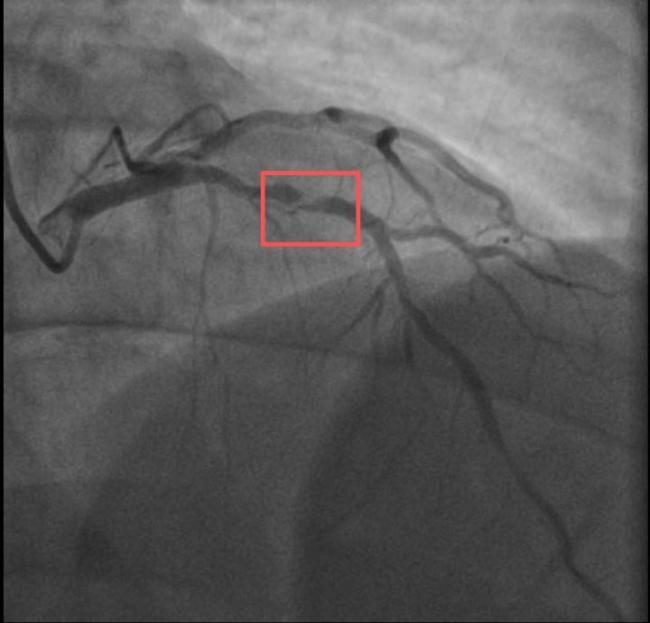

男子打10分钟羽毛球后心梗 剧烈运动成诱因

两个38岁的宝爸同一天因为急性心梗被送进医院,且都发生在剧烈运动后。一位陪孩子打了10分钟羽毛球,另一位陪孩子爬了一次山。这两位父亲的情况引发了人们的关注。孙先生是一位羽毛球教练,身高173cm,体重约90KG